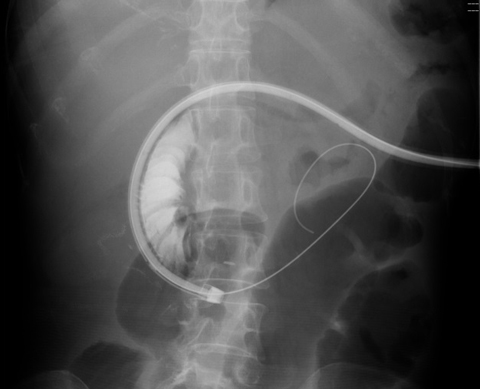

通常の腸閉塞と同様、イレウス管による腸管減圧が腹部膨満感の改善に有用です。ただしCIPOは慢性的な腸閉塞状態ですので、大半の症例で持続的な減圧が必要になります。通常イレウス管は鼻から挿入し、先端を小腸まで進めますが(下図)、咽頭痛や鼻腔出血などの患者様の負担が大きく、また入院も長期化してしまう事があり、この点が最大の課題です。

図3. 従来の消化管減圧法(イレウス管)

図5. PEG-J挿入の実際

レントゲン透視下で胃瘻の瘻孔(穴)から十二指腸→小腸に挿入した柔らかいガイドワイヤーに沿ってチューブを進めていく(左)。

上部小腸(空腸)まで進めて終了(右)。